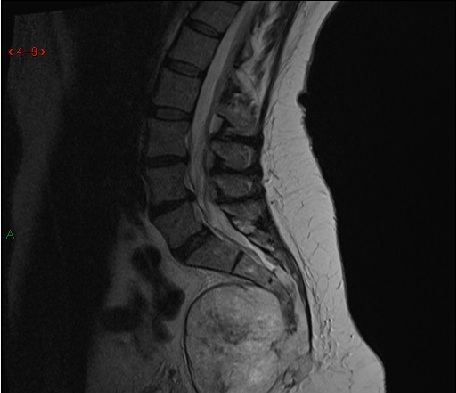

MRI lumbosacral spine dari 23 thn perempuan dengan LBP parah menjalar ke kaki kanannya. Gambar kiri adalah T2 sagital dan gambar kanan adalah axial T2. Nerve root manakah kemungkinan terbesar yg terkompres oleh diskus herniasi?

A. Melintasi L5 nerve roots

B. Keluar dari L5 nerve roots

C. Melintasi L4 nerve roots

D. Keluar dari S1 nerve roots

E. Melintasi S1 nerve roots

The correct answer is the traversing S1 nerve roots.

The MRI shows a focal right paracentral posterior herniation of the L5-S1 intervertebral disc. The herniated disc material causes mild narrowing of the spinal canal and severe narrowing of the lateral recess at L5-S1. The S1 nerve roots traverses at the L5-S1 level, and is therefore the most likely to be compressed by this disc herniation. The traversing L4 nerve root and L5 nerve root have are found at levels above this lesion. The exiting nerve roots at the L5-S1 level (the L5 nerve roots) will already be lateral to the disc herniation and will not be compressed.